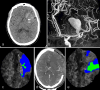

Our study aimed to evaluate the postoperative outcome of patients with unruptured giant middle cerebral artery (MCA) aneurysm revealed by intracranial hypertension associated to midline brain shift. From 2012 to 2022, among the 954 patients treated by a microsurgical procedure for an intracranial aneurysm, our study included 9 consecutive patients with giant MCA aneurysm associated to intracranial hypertension with a midline brain shift. Deep hypothermic circulatory flow reduction (DHCFR) with vascular reconstruction was performed in 4 patients and cerebral revascularization with aneurysm trapping was the therapeutic strategy in 5 patients. Early (< 7 days) and long term clinical and radiological monitoring was done. Good functional outcome was considered as mRS score ≤ 2 at 3 months. The mean age at treatment was 44 yo (ranged from 17 to 70 yo). The mean maximal diameter of the aneurysm was 49 mm (ranged from 33 to 70 mm). The mean midline brain shift was 8.6 mm (ranged from 5 to 13 mm). Distal MCA territory hypoperfusion was noted in 6 patients. Diffuse postoperative cerebral edema occurred in the 9 patients with a mean delay of 59 h and conducted to a postoperative neurological deterioration in 7 of them. Postoperative death was noted in 3 patients. Among the 6 survivors, early postoperative decompressive hemicraniotomy was required in 4 patients. Good functional outcome was noted in 4 patients. Complete aneurysm occlusion was noted in each patient at last follow-up. We suggest to discuss a systematic decompressive hemicraniotomy at the end of the surgical procedure and/or a partial temporal lobe resection at its beginning to reduce the consequences of the edema reaction and to improve the postoperative outcome of this specific subgroup of patients. A better intraoperative assessment of the blood flow might also reduce the occurrence of the reperfusion syndrome.